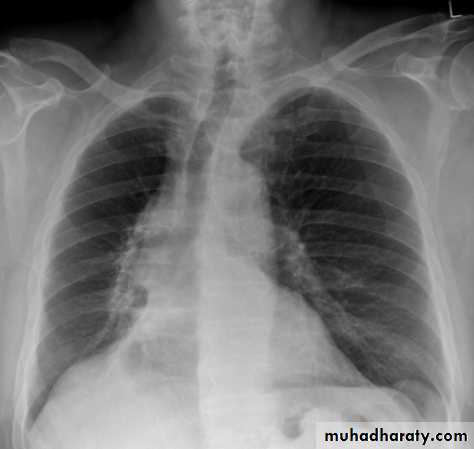

Right upper lobe collapse has distinctive features, and is usually easily identified on frontal chest radiographs .

Radiographic features

Chest radiograph

Collapse of the right upper lobe is usually relatively easy to identify on frontal radiographs. Features consist of :

increased density in the upper medial aspect of the right hemithorax

elevation of the horizontal fissure

loss of the normal right medial cardiomediastinal contour

elevation of the right hilum

hyperinflation of the right middle and lower lobe result in increased translucency of the mid and lower parts of the right lung

right juxtaphrenic peak

A common cause of lobar collapse is a hilar mass. When a right hilar mass is combined with collapse of the right upper lobe, the result is an S shape to elevated horizontal fissure. This is known as Golden S sign .

Non-specific signs indicating right sided atelectasis are also usually present including:

elevation of the hemidiaphragm

crowding of the right sided ribs

shift of the mediastinum and trachea to the right